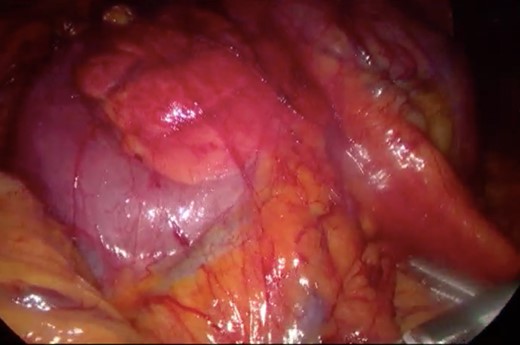

Initially, conservative management was adopted with some improvement of patient’s nutrition condition. However, as symptoms persisted, surgical treatment was recommended. Our surgical approach was a laparoscopic duodenojejunostomy with a latero-lateral stapled anastomosis between jejunum (30 cm from Treitz’s angle) and the second portion of the duodenum (Figs 5–9). The patient recovered with no pain but with a delay in diet acceptance. An upper GI contrast study was performed on the fifth post-operative day revealing a distended stomach with gastric emptying delay, but with unobstructed anastomosis, therefore without stenosis or leaks (Fig. 10). She was discharged home after 8 days with liquid diet and digestive transit restored. After 3 months of follow-up, the patient gained some weight and remained asymptomatic.

Surgery—initial laparoscopic view with distended stomach and proximal portions of duodenum.